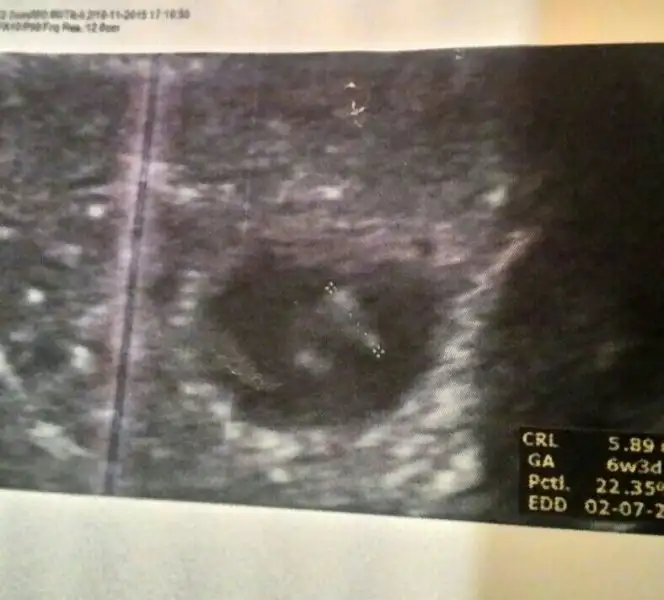

Bana burada erkek dediler ya bi kaç sayfa önce

Peki şimdi tutması gereken Ramzi teorisine gore benim bebeğim ne olur kiSu plesantadan anlamiyom hic valla ama ramzi teorisi cogu kiside tuttu. Elbet yanilma payi olcak. Oyle olmasaydi doktorlar 7.haftada cinsiyetini soylerdi direk. 10 kisiden 8i 9u tutiyorsa iyi bi orndir bence

Ole dediysem ole derim tekrar ben baskada bisey bilmiyorum bi de ovulasyon gununu bilenler icin ay cekimine gore bise var o kdr ondada cok yuksekmis tahminin tutma olasiligi ve biyolojik takvim. Heleki cocuklariniz varsa baska saglamasini bile yapabiliyosunuz.tutiyomu tutmuyomuPeki şimdi tutması gereken Ramzi teorisine gore benim bebeğim ne olur kidlrsordn canım sen bana fotolara gore erkek demistin

Benim usg mi sordun sanıp, benimki karından yazmışım pardon canım. Bu fotolar yabancı sitelerden alıntı. Haklısın bunlar vajinal usg. Plasenta sağda görünüyorsa aslında solda doğru canım.Vajinalsa cnm bebek solda olmuş olmuyor mu bu resimde bebek sağda ama vajinal olduğu için bebek solda olmuş olmuyor mu,plasenta zaten soldaymis.

Vajinalsa cnm bebek solda olmuş olmuyor mu bu resimde bebek sağda ama vajinal olduğu için bebek solda olmuş olmuyor mu,plasenta zaten soldaymis.

Erkeğe benziyo çünkü solda. Yani aslında sağda karnına tuttuğunda.Canım bunda plesenta nerde...